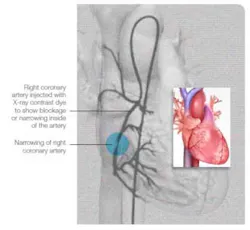

Broken heart syndrome may be misdiagnosed as a heart attack because the symptoms and test results are similar. Actually, tests show dramatic changes in rhythm and blood substances that are typical of a heart attack. Dissimilar to a heart attack, there is usually no evidence of blocked heart arteries in broken heart syndrome.(1) In this syndrome, a part of the heart temporarily enlarges and doesn’t pump well, while the rest of your heart functions normally or with even more forceful contractions. Researchers are just starting to learn the causes, and how to diagnose and treat it. Broken heart syndrome can lead to severe, short-term heart muscle failure, but is usually treatable. Most people who experience it make a full recovery within weeks, and they’re at low risk for it happening again. In rare cases in can be fatal.For more information and case reports, read about Takotsubo Cardiomyopathy, or Broken-Heart Syndrome in the Texas Heart Institute Journal.(6)